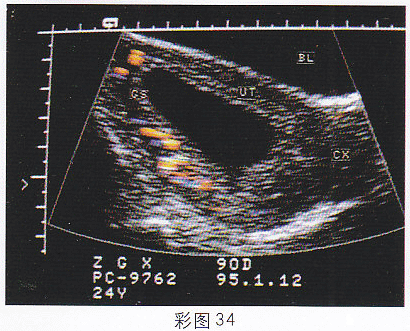

1.女,25歲,停經55天,腹痛、陰道出血1周。尿妊娠試驗陰性。結合超聲圖像(彩圖34),最可能的診斷為

正確答案:D 解題思路:宮腔內可見無回聲暗區,其內未見胚芽及胎心搏動。患者有停經,腹痛,陰道流血等流產癥狀,尿HCG陰性。